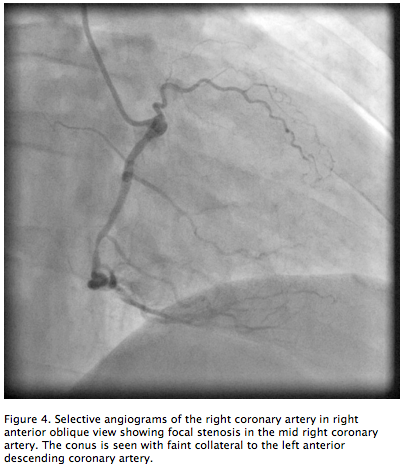

Figure 4. Selective angiograms of the right coronary artery in right anterior oblique view showing focal stenosis in the mid right coronary artery. The conus is seen with faint collateral to the left anterior descending coronary artery (click thumbnail to view larger image).

There were two collateral systems supplying the LAD. These were: (1) the DSA originating from the right coronary cusp giving collaterals to the septal branch and filling the LAD to the apex (Figures 2 and 3); and (2) collaterals from the conus branch of the RCA reaching the first septal branch of the LAD (Figures 3 and 4). Both collateral systems were small in size. The dominant RCA had a focal segment of 60%-70% stenosis (Figure 4). Left ventricular systolic function was normal. The left circumflex (LCX) had mild disease. The patient underwent successful bypass surgery with grafts to the LAD as well as RCA and had uneventful recovery.